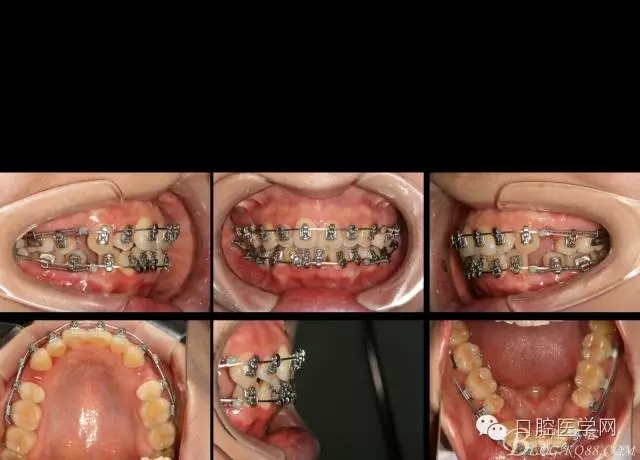

2016.6.7 第二次復(fù)診效果 上頜繼續(xù),只是將弓絲末端變長的弓絲剪斷重新回彎,其他沒有做任何處理。下頜將右側(cè)的拉簧拆掉,在右下1與3之間推簧,調(diào)整中線,其余沒動(dòng)。

矯正到目前,矯正開始三個(gè)月四天,矯正比較平穩(wěn),拔牙間隙關(guān)閉接近三分之二。矯正效果明顯。每次復(fù)診處理簡潔,椅旁時(shí)間幾分鐘。大大減少醫(yī)生工作壓力,矯正療程大大縮短,是個(gè)很好的技術(shù)。

如果,矯正再輔助種植支抗,穩(wěn)定主弓絲平面以及轉(zhuǎn)移牽引力,矯正將更加平順穩(wěn)定。